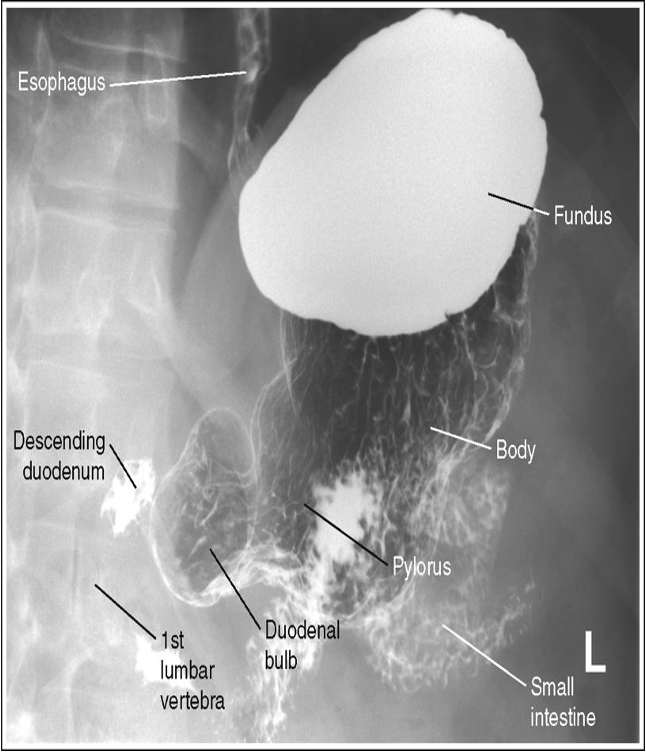

Recumbent RAO - Visualized the pyloric canal and duodenal bulb. No superimposition of pylorus and duodenal bulb. Gastric peristalsis is more active in this position.

CR - At the level 1-2 inches above lower rib margin (L1-L2) Midway between the vertebrae nd the lateral border of the elevated side

PA Stomach with proper positioning

Oblique stomach with proper positioning

Lateral stomach with proper positioning